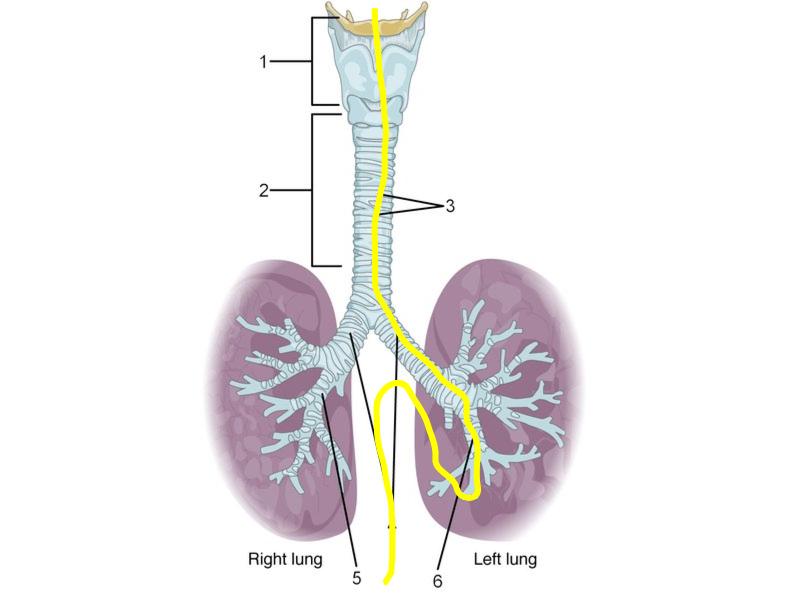

Go with the flow

Trace the air flow of respiratory system starting with the nostrils.What path does a molecule of oxygen take to reach the blood?

What sights will it see along the way?

1. Outside air

Trachea

Bronchi - Transitions

- Intrapulmonary bronchi

- Irregular cartilage

- Respiratory epithelium